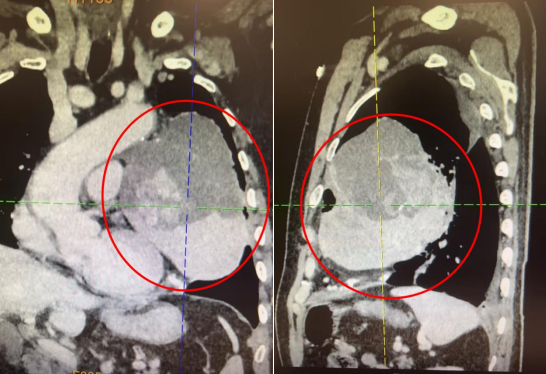

133 mm 的巨大肿瘤

几乎占满左侧胸腔

体积大、侵犯广、牵涉血管神经多

严重压迫心脏、肺动静脉

左上肺被挤到快「消失了」

10 月 9 日,叶惠龙总院长与手术团队紧密协作,凭着高超的技术、细致的操作、扎实的功底、丰富的经验,高度专注,如履薄冰地将肿瘤与周围组织、脏器仔细分离,经过两个多小时,约 133 mmX111 mmX118 mm 大小的肿瘤被完整剥离,手术十分顺利,病理报告 AB 胸腺瘤。